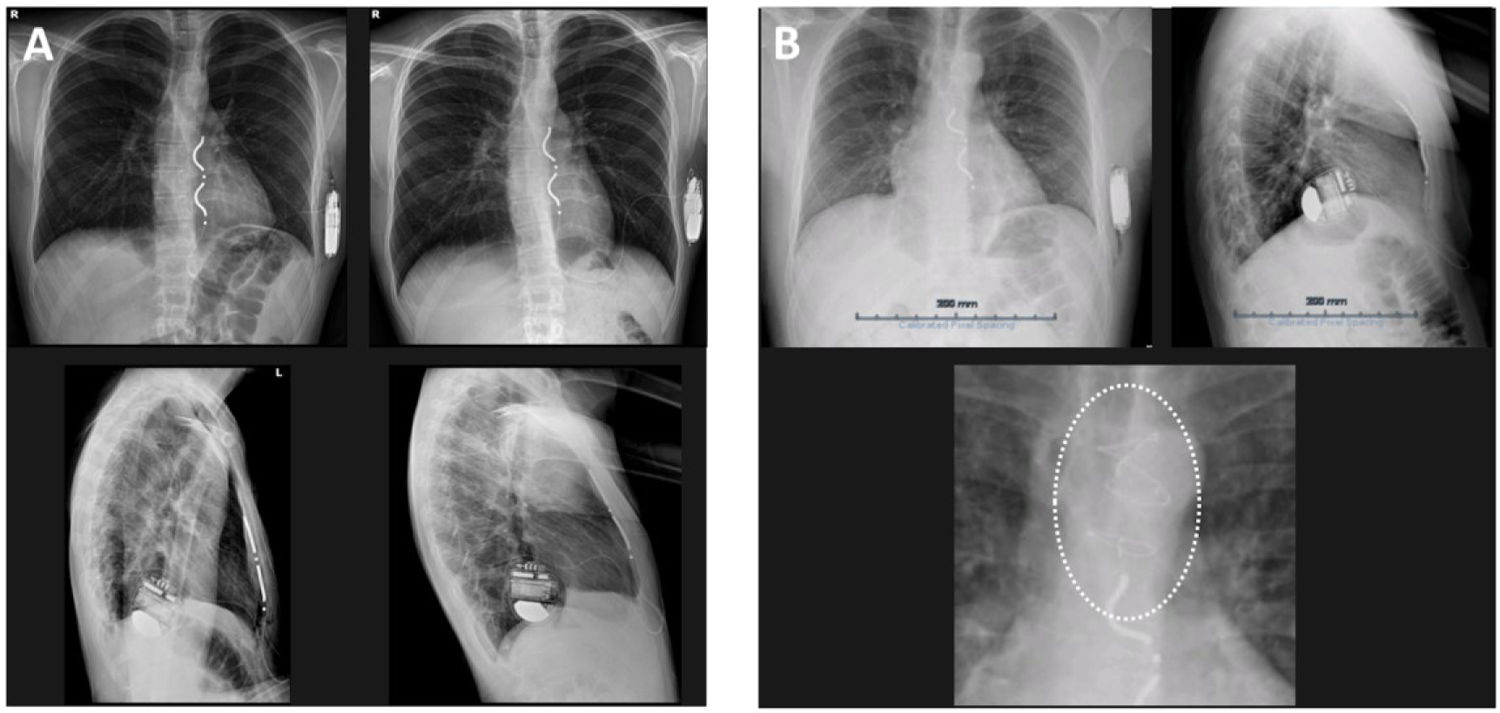

Chest X-rays confirmed stable lead and generator positioning in all cases. A minor posterior tilting of the lead or a discrete shifting to the right side was noted in two patients, one of them with previous partial sternotomy. Wound healing was uneventful and no infections were documented during hospitalization or during follow-up.

No lead migration, sensing failure, or battery-related issues were observed. Impedance trends and R-wave amplitudes remained stable. Chest x-rays at follow-up confirmed unchanged or minimally changed lead trajectory and generator positioning (Figure 4).

Chest X-ray imaging at follow-up. (A) Anteroposterior and left lateral thoracic radiographs obtained at discharge (images on the left) and at three-month follow-up, confirming unchanged lead trajectory and generator positioning. (B) This patient had a previous partial sternotomy from a previous surgery to remove a thymoma and was selected for an EV-ICD. The chest X-ray shows a minor tilting of the lead towards the right side that did not affect the final parameters.